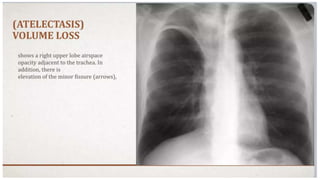

THORACO-ABDOMINAL SIGN